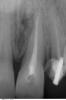

SergioS Опубликовано 27 апреля, 2013 Поделиться Опубликовано 27 апреля, 2013 Уважаемые коллеги, подскажите как бы кто поступил в данной ситуации:21 наружняя резорбция, в канале цемент, при попытке ревизии выскочили в резорбцию, инструмент заклинил и остался. В канале Vitapex, последние 2 мм не пройдены.У нас варианта 2:1.Пломбировка альфа-гуттой, хирургическим путем извлечь инструмент, MTA, остеопластический материал и под наблюдение.2..Пломбировка альфа-гуттой, резекция,MTA, остеопластический материал и под наблюдение.Снимки. Ссылка на комментарий

DmitrySH Опубликовано 27 апреля, 2013 Поделиться Опубликовано 27 апреля, 2013 КАК в резорбции можно сломать инструмент? Честно, больше на перфо похоже. Ссылка на комментарий

Мaxim Опубликовано 27 апреля, 2013 Поделиться Опубликовано 27 апреля, 2013 резорбция может там и есть,другое дело как вам удалось там сделать перфо?резекция не поможет так как от корня останется гулькин хвост.имхоДлина канала 24.7 мм.длина корня,попадающая под резекцию 3 мм.а причина "перфы" - изгиб профайла и излишняя с моей стороны уверенность..и работа по предварительному снимку ... Ссылка на комментарий